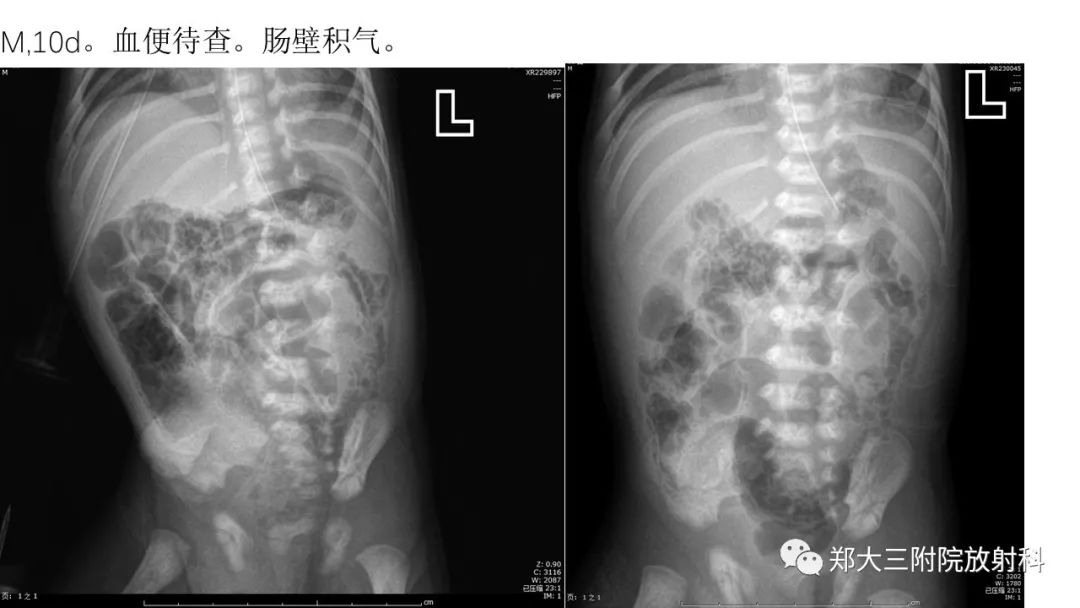

医学百科网 | YxBaike.Com •NEC(necrotizing enterocolitis)是一种获得性的新生儿肠功能紊乱,是由于发育不全的肠壁黏膜、血管受到缺血、感染、代谢等因素联合作用的刺激,导致严重肠损伤。NNEC是新生儿最常见的需急诊手术的肠道疾病。

•NEC多见于生后2-3周,以早产儿、低体重儿、人工喂养儿多见,特别是胎膜早破产程延长或出生时有窒息的新生儿。•早期即可有腹胀、肠鸣音减弱或消失。•呕吐,呕吐物可呈咖啡样或含有胆汁。•血便,常呈洗肉水样,量较多,腥臭。腹泻,体温不稳定,精神反应差,拒食。

•NEC特征性的影像表现主要为肠壁积气及门静脉积气,如果临床上患儿有腹胀、血便、肠鸣音消失等病史,应高度怀疑NEC的可能。 医学百科网 | YxBaike.Com